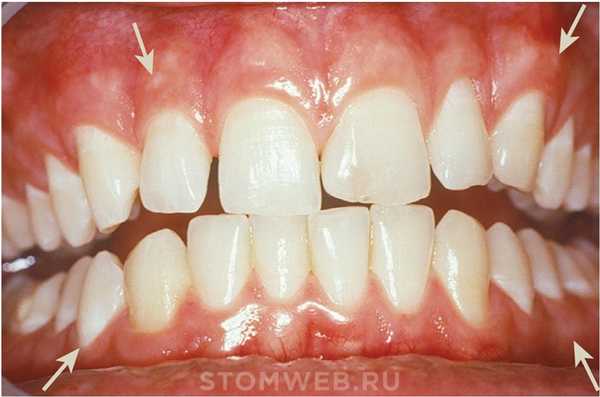

Рисунок 2-1 Нормальная десна у молодого взрослого человека. Обратите внимание на разграничение (мукогингивальная линия) (стрелки) между прикрепленной десной и более темной альвеолярной слизистой оболочкой.

Маргинальная, или неприкрепленная, десна представляет собой край или границу десны, окружающую зубы в виде воротника (рисунки 2-1 и 2-2). Примерно в 50% случаев она отделена от прилегающей прикрепленной десны с помощью неглубокого линейного углубления - свободного десневого желобка. Обычно около 1 мм шириной, маргинальная десна образует стенку десневой борозды. Она может быть отделена от поверхности зуба пародонтальным зондом.